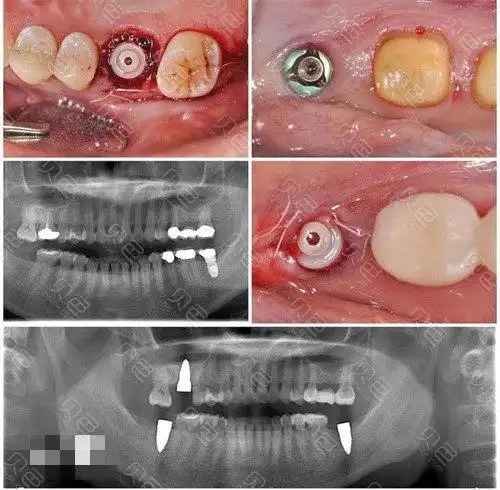

即刻拔牙后做半口瑞士士卓曼钛锆亲水种植牙,花了8.8万

种植牙修复过程中常出现的并发症及其处理_医学界-助力医生临床决策和